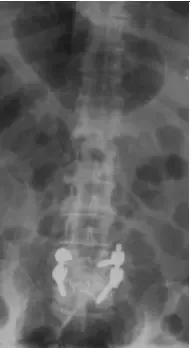

X-rays and MRI of the Lumbar spine showed L4-5 degenerative spondylolisthesis

and severe spinal stenosis.